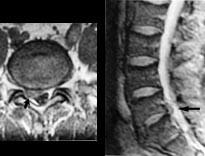

MR gir verdifull informasjon hos pasienter med degenerative lidelser i columna. En av de store fordelene ved MR er at bein og bløtdeler kan demonstreres i samme bilde, men atskilles pga. forskjellige signaler. Foreløpig kan det være et problem at oppløsningen i bildene ikke er så god som i konvensjonelle røntgenbilder. Enkelte detaljer kan derfor fremstilles bedre ved konvensjonelle radiologiske metoder, f.eks. rotskjeder ved myelografi. Prolaps kan som oftest fremstilles tilfredsstillende med CT (19), men i de fleste tilfeller er MR-bildene lettere å tolke (fig 6) (5).